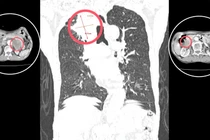

U tuyến thượng thận (UTTT) là bệnh nguy hiểm không chỉ gây ảnh hưởng tới sức khoẻ, tinh thần mà còn khiến chất lượng cuộc sống giảm nghiêm trọng, dễ biến chứng tử vong. Nhờ sự chuyển giao kỹ thuật từ Bệnh viện Hữu nghị Việt Đức, Bệnh viện Đa khoa Thanh Hóa đã làm chủ kỹ thuật này, mổ cho bệnh nhân an toàn, nhanh hồi phục